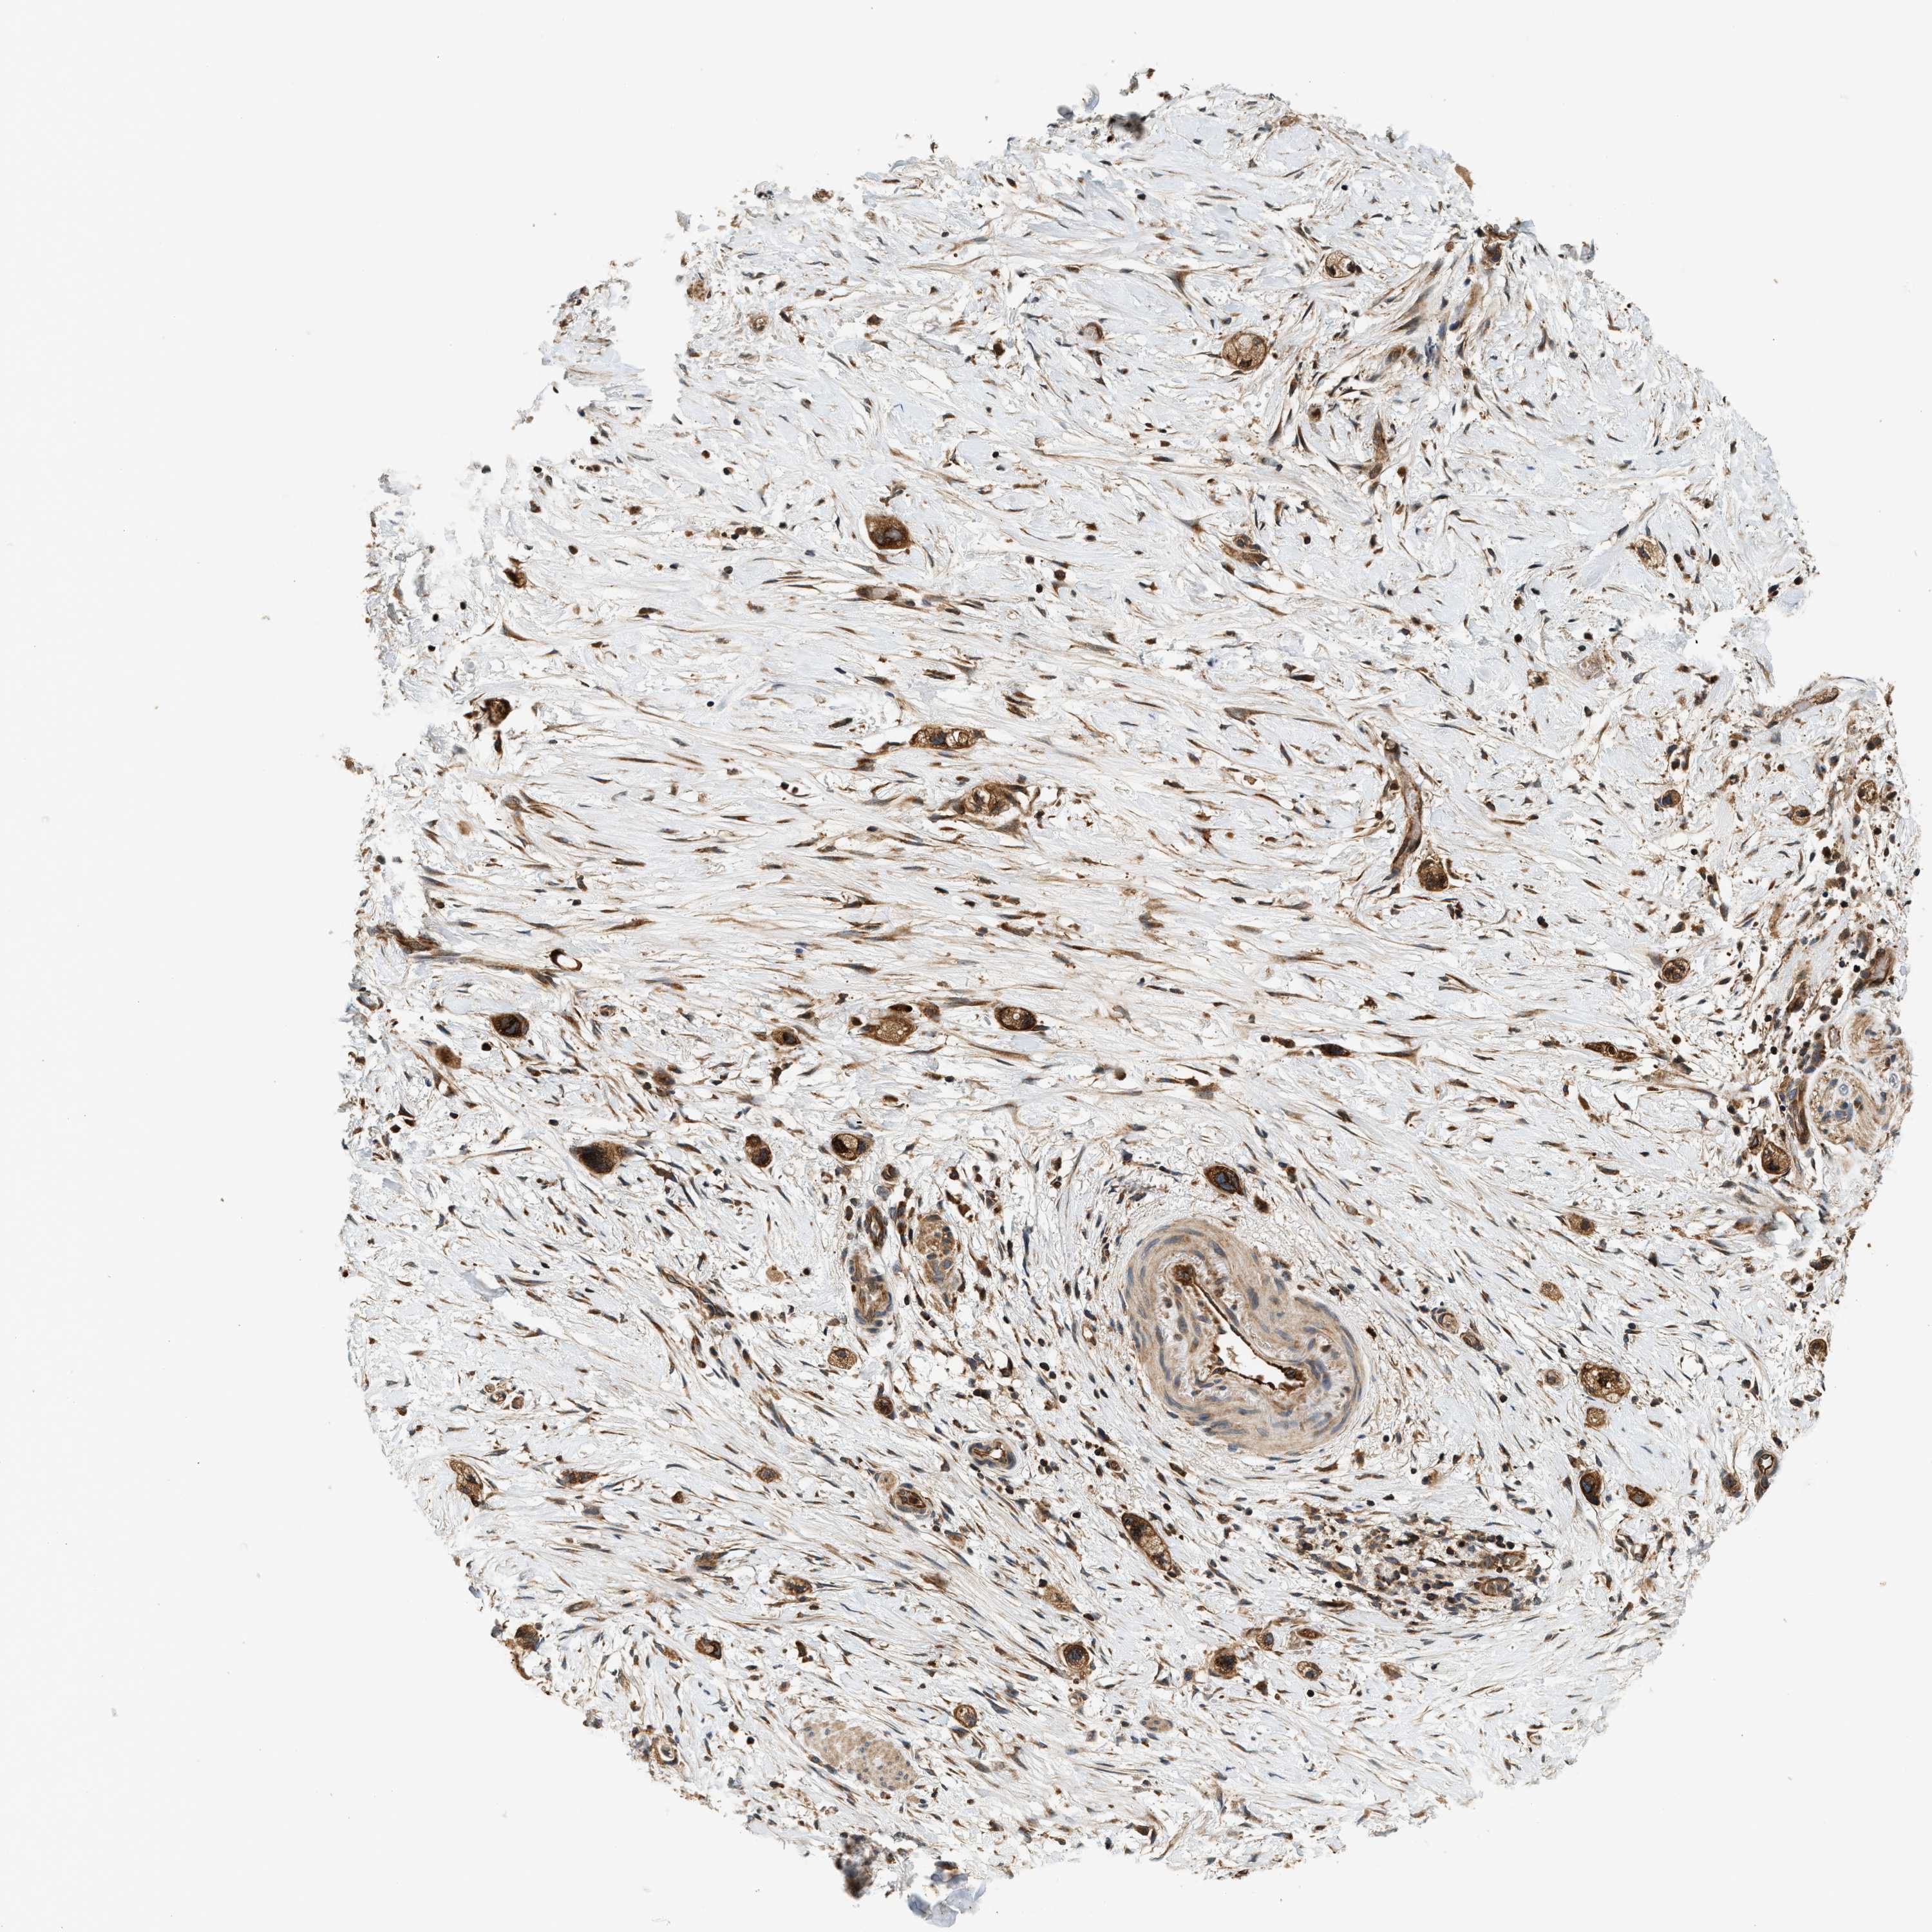

STOMACH CANCER - Protein expressioni

A mouse-over function shows sample information and annotation data. Click on an image to view it in a full screen mode. Samples can be filtered based on level of antibody staining by selecting one or several of the following categories: high, medium, low and not detected. The assay and annotation is described here.

Note that samples used for immunohistochemistry by the Human Protein Atlas do not correspond to samples in the TCGA dataset.

Antibody stainingi

Antibody staining in the annotated cell types in the current human tissue is reported as not detected, low, medium, or high, based on conventional immunohistochemistry profiling in selected tissues. This score is based on the combination of the staining intensity and fraction of stained cells.

Each image is clickable and will lead to virtual microscopy that enables deeper exploration of all samples and also displays staining intensity scores, fraction scores and subcellular localization as well as patient and tissue information for each sample.

Antibody HPA021318

Antibody HPA021319

Staining

High

Medium

Low

Not detected

Intensity

Strong

Moderate

Weak

Negative

Quantity

>75%

75%-25%

<25%

None

Location

Nuclear

Cytoplasmic/membranous

Cytoplasmic/membranous,nuclear

Adenocarcinoma, NOS